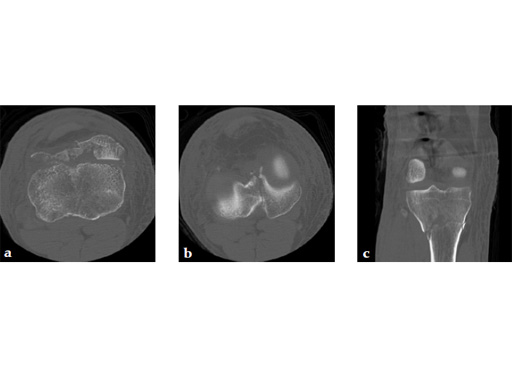

Staged management with initial rodding of femur and placement of spanning knee external fixator with closed manipulative reduction of tibial plateau (Fig 3).